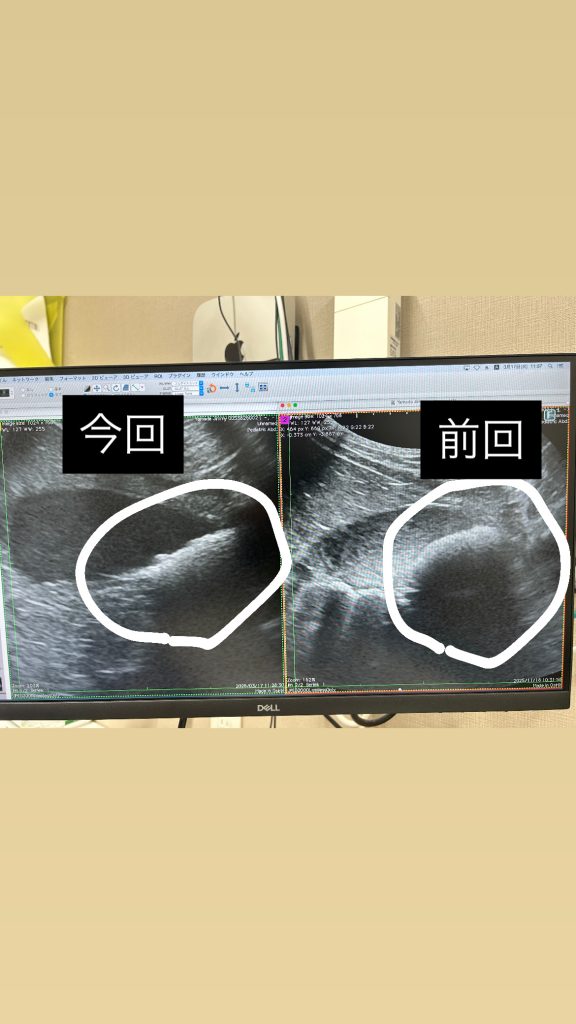

先生に褒められた!前回よりめちゃくちゃ良くなっていい膀胱になってます!!って!!

丸で囲ってるとこがじみの砂。

前回より確実に減ってる!!